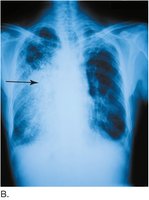

Atelectasis refers to the collapse of part or all of a lung, resulting in reduced gas exchange and visible as a hazy area on chest x-ray.

Pneumonia

Pneumonia is an infection of the lung tissue, visible on x-ray as a dense, gray-white area. It can be caused by bacteria, viruses, or fungi.

Chest x-rays are commonly used to visualize lung structure and diagnose conditions such as pneumonia, atelectasis, and tumors.